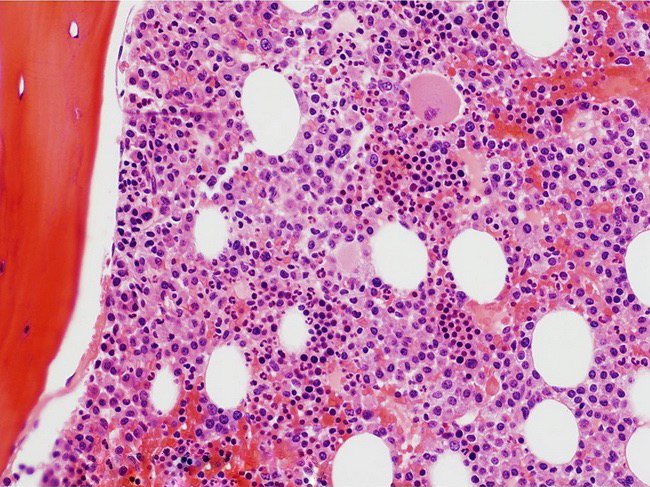

Microscopic (histologic) description

- Core biopsy (Am J Clin Path 1987;87:342):

- Interstitial clusters, nodules or sheets of plasma cells

- Areas of bone marrow may be spared with preserved hematopoiesis, other cases may have diffuse involvement and markedly suppressed hematopoiesis

- Prominent osteoclastic activity may be seen

- IHC to quantify plasma cells (CD138), stains for Ig kappa and lambda to establish clonality

Microscopic (histologic) images

Contributed by Genevieve M. Crane, M.D., Ph.D. and Tapan Bhavsar, M.D., Ph.D.